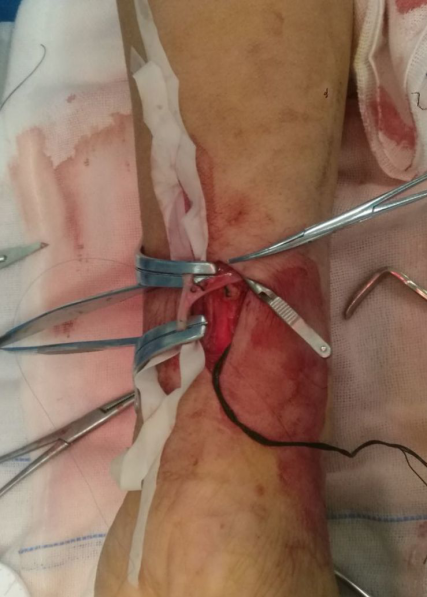

尺动脉和贵要静脉吻合成功

吻合成功并松开动静脉血管夹以后,可触及贵要静脉震颤,但因为尺动脉迂曲,感觉尺动脉被贵要静脉向近心端拉拽,导致吻合口近心端成角较重,震颤强度总感觉不够。(又没来得及留图)

最后在A、B两点用血管缝合线把尺动脉和组织挂了两针,把吻合口成角改成尺动脉成角,减小吻合口角度,感觉震颤较前明显增强。